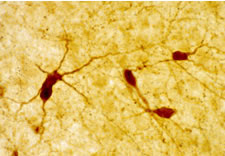

Detection of rat neuropeptide Y by immunohistochemistry. Sample: Rat paraventricular nucleus, cortex, and caudate putamen. Primary antibody: Anti-Neuropeptide Y Rabbit pAb (Cat. No. PC223L) (1:10,000). Detection: fluorescence.

Antibody specificity was examined in the rat cortex, caudate putamen, and paraventricular nucleus. Staining is completely eliminated by pretreatment of antibody with neuropeptide Y (10-6M). Preabsorption with avian pancreatic polypeptide, β-endorphin, cholecystokinin, peptide YY, somatostatin, or vasoactive intestinal peptide resulted in no loss of immunostaining. Antibody should be titrated for optimal results in individual systems.